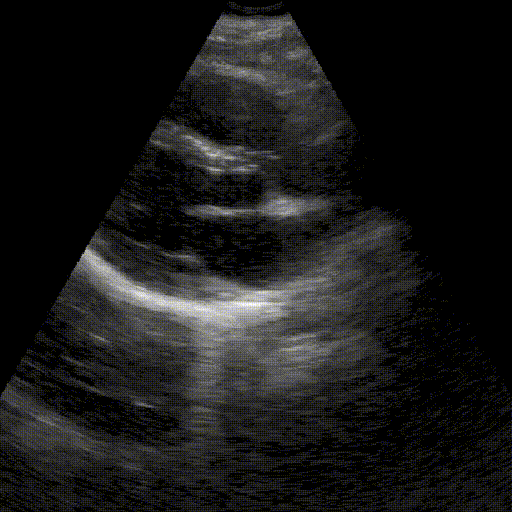

Objectif

Identifier et quantifier un syndrome interstitiel diffus. Bien qu'évocateur d'un œdème pulmonaire aigu (OAP) en contexte d'urgence, ce signe doit être confronté à la clinique pour écarter les autres étiologies (pneumopathie, fibrose, SDRA...).

Points clés

- Reconnaissance des artefacts en "queue de comète" (lignes B) : verticaux, partant de la ligne pleurale.

- Quantification : Présence de multiples lignes B (> 3) par champ, comme illustré sur l'image.

- Identification des formes sévères : Lignes B coalescentes (aspect de "poumon blanc") et effacement des lignes A.